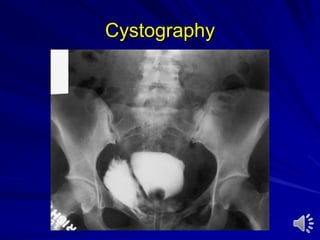

Cystography

Ascending And Micturating Cystourethrography Catheterin the urethra and fill it with contrast medium Catheter in the bladder and fill it with contrast medium Indications: – Trauma – Vesicoureteral reflux – Posterior urethral valve – Stricture urethra – Stress incontinence – Fistula